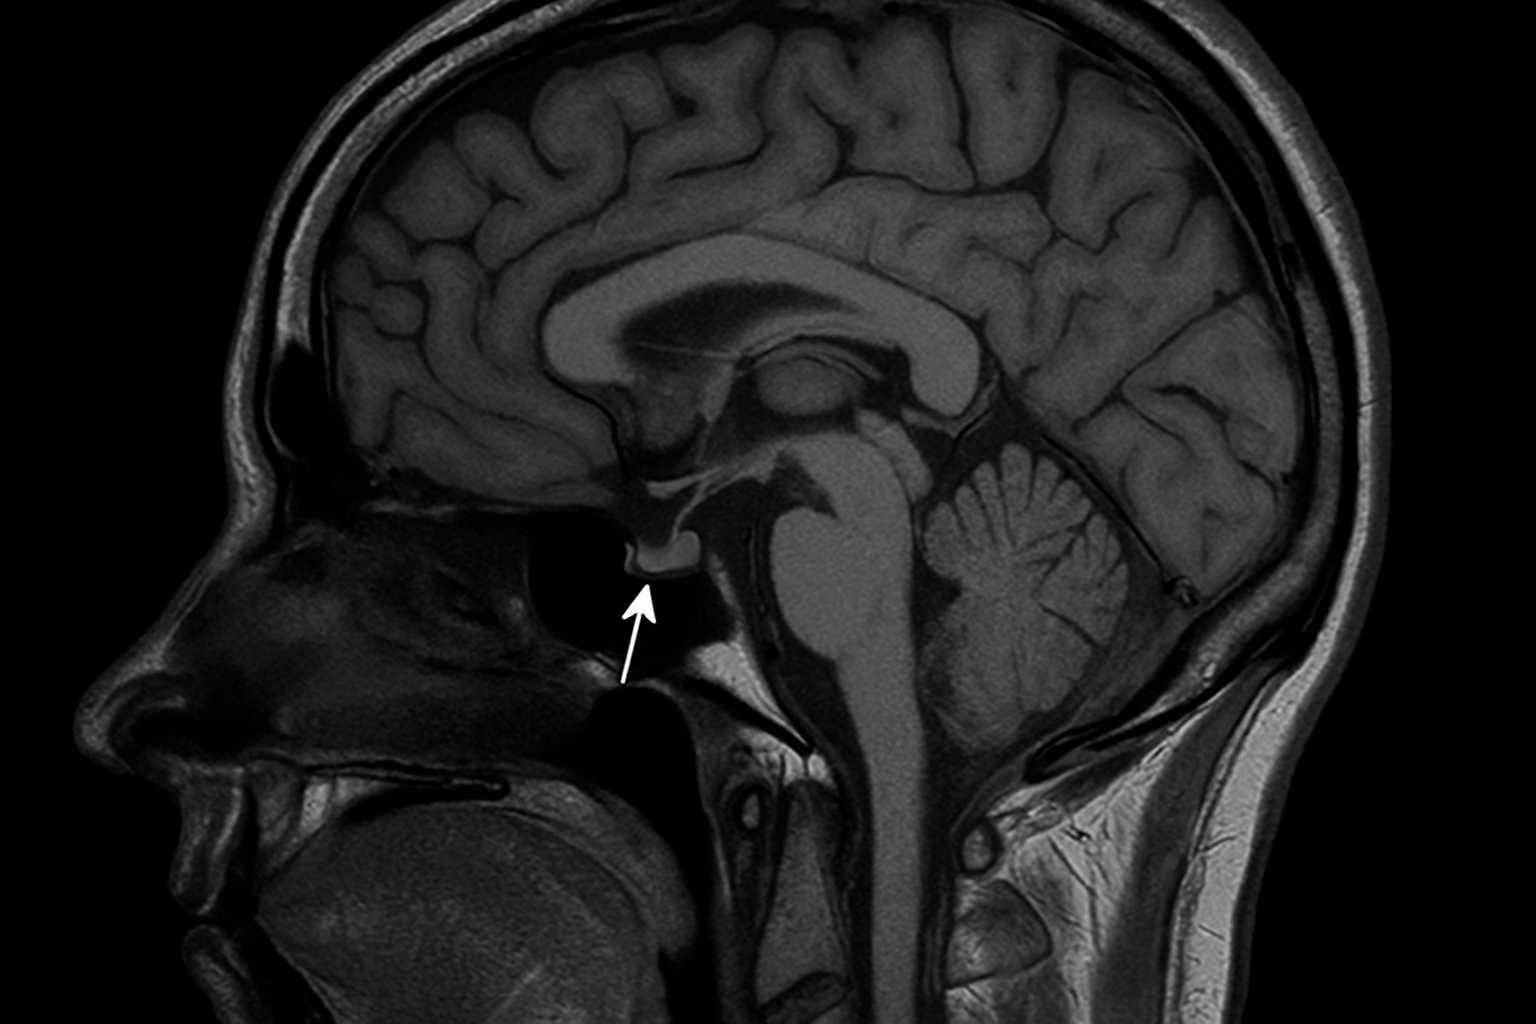

Гипофиз в процессе исследования невозможно отделить и обследовать отдельно от всего мозга, поэтому при МРТ получают срезы мозга в различных проекциях. Для более детального просмотра увеличивают отдельные зоны. Такая процедура требуется пациенту, если врачу сложно установить диагноз, к примеру, нечеткая симптоматика.

МРТ гипофиза — точное исследование. С его помощью можно выявить крупные и мелкие новообразования. Аденомы в гипофизе могут быть нескольких типов: макроаденомы, микроаденомы. Размер вторых может быть не больше 6мм. Найти и проанализировать их достаточно сложно, но МРТ поможет это сделать с максимальной точностью. Чем выше будет напряжение магнитного поля, тем четче выходит изображение. Причем даже в такой ситуации процедура не будет болезненной, и пациент не облучается. На все исследование придется потратить максимум полчаса времени.